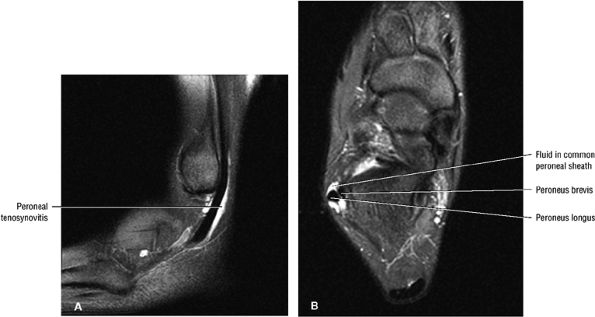

|